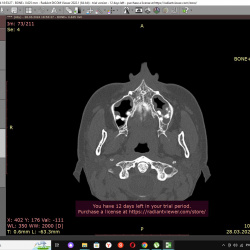

Добрый день. подскажите пожалуйста как описать верхнечелюстные пазухи... пролабирование зубов ???